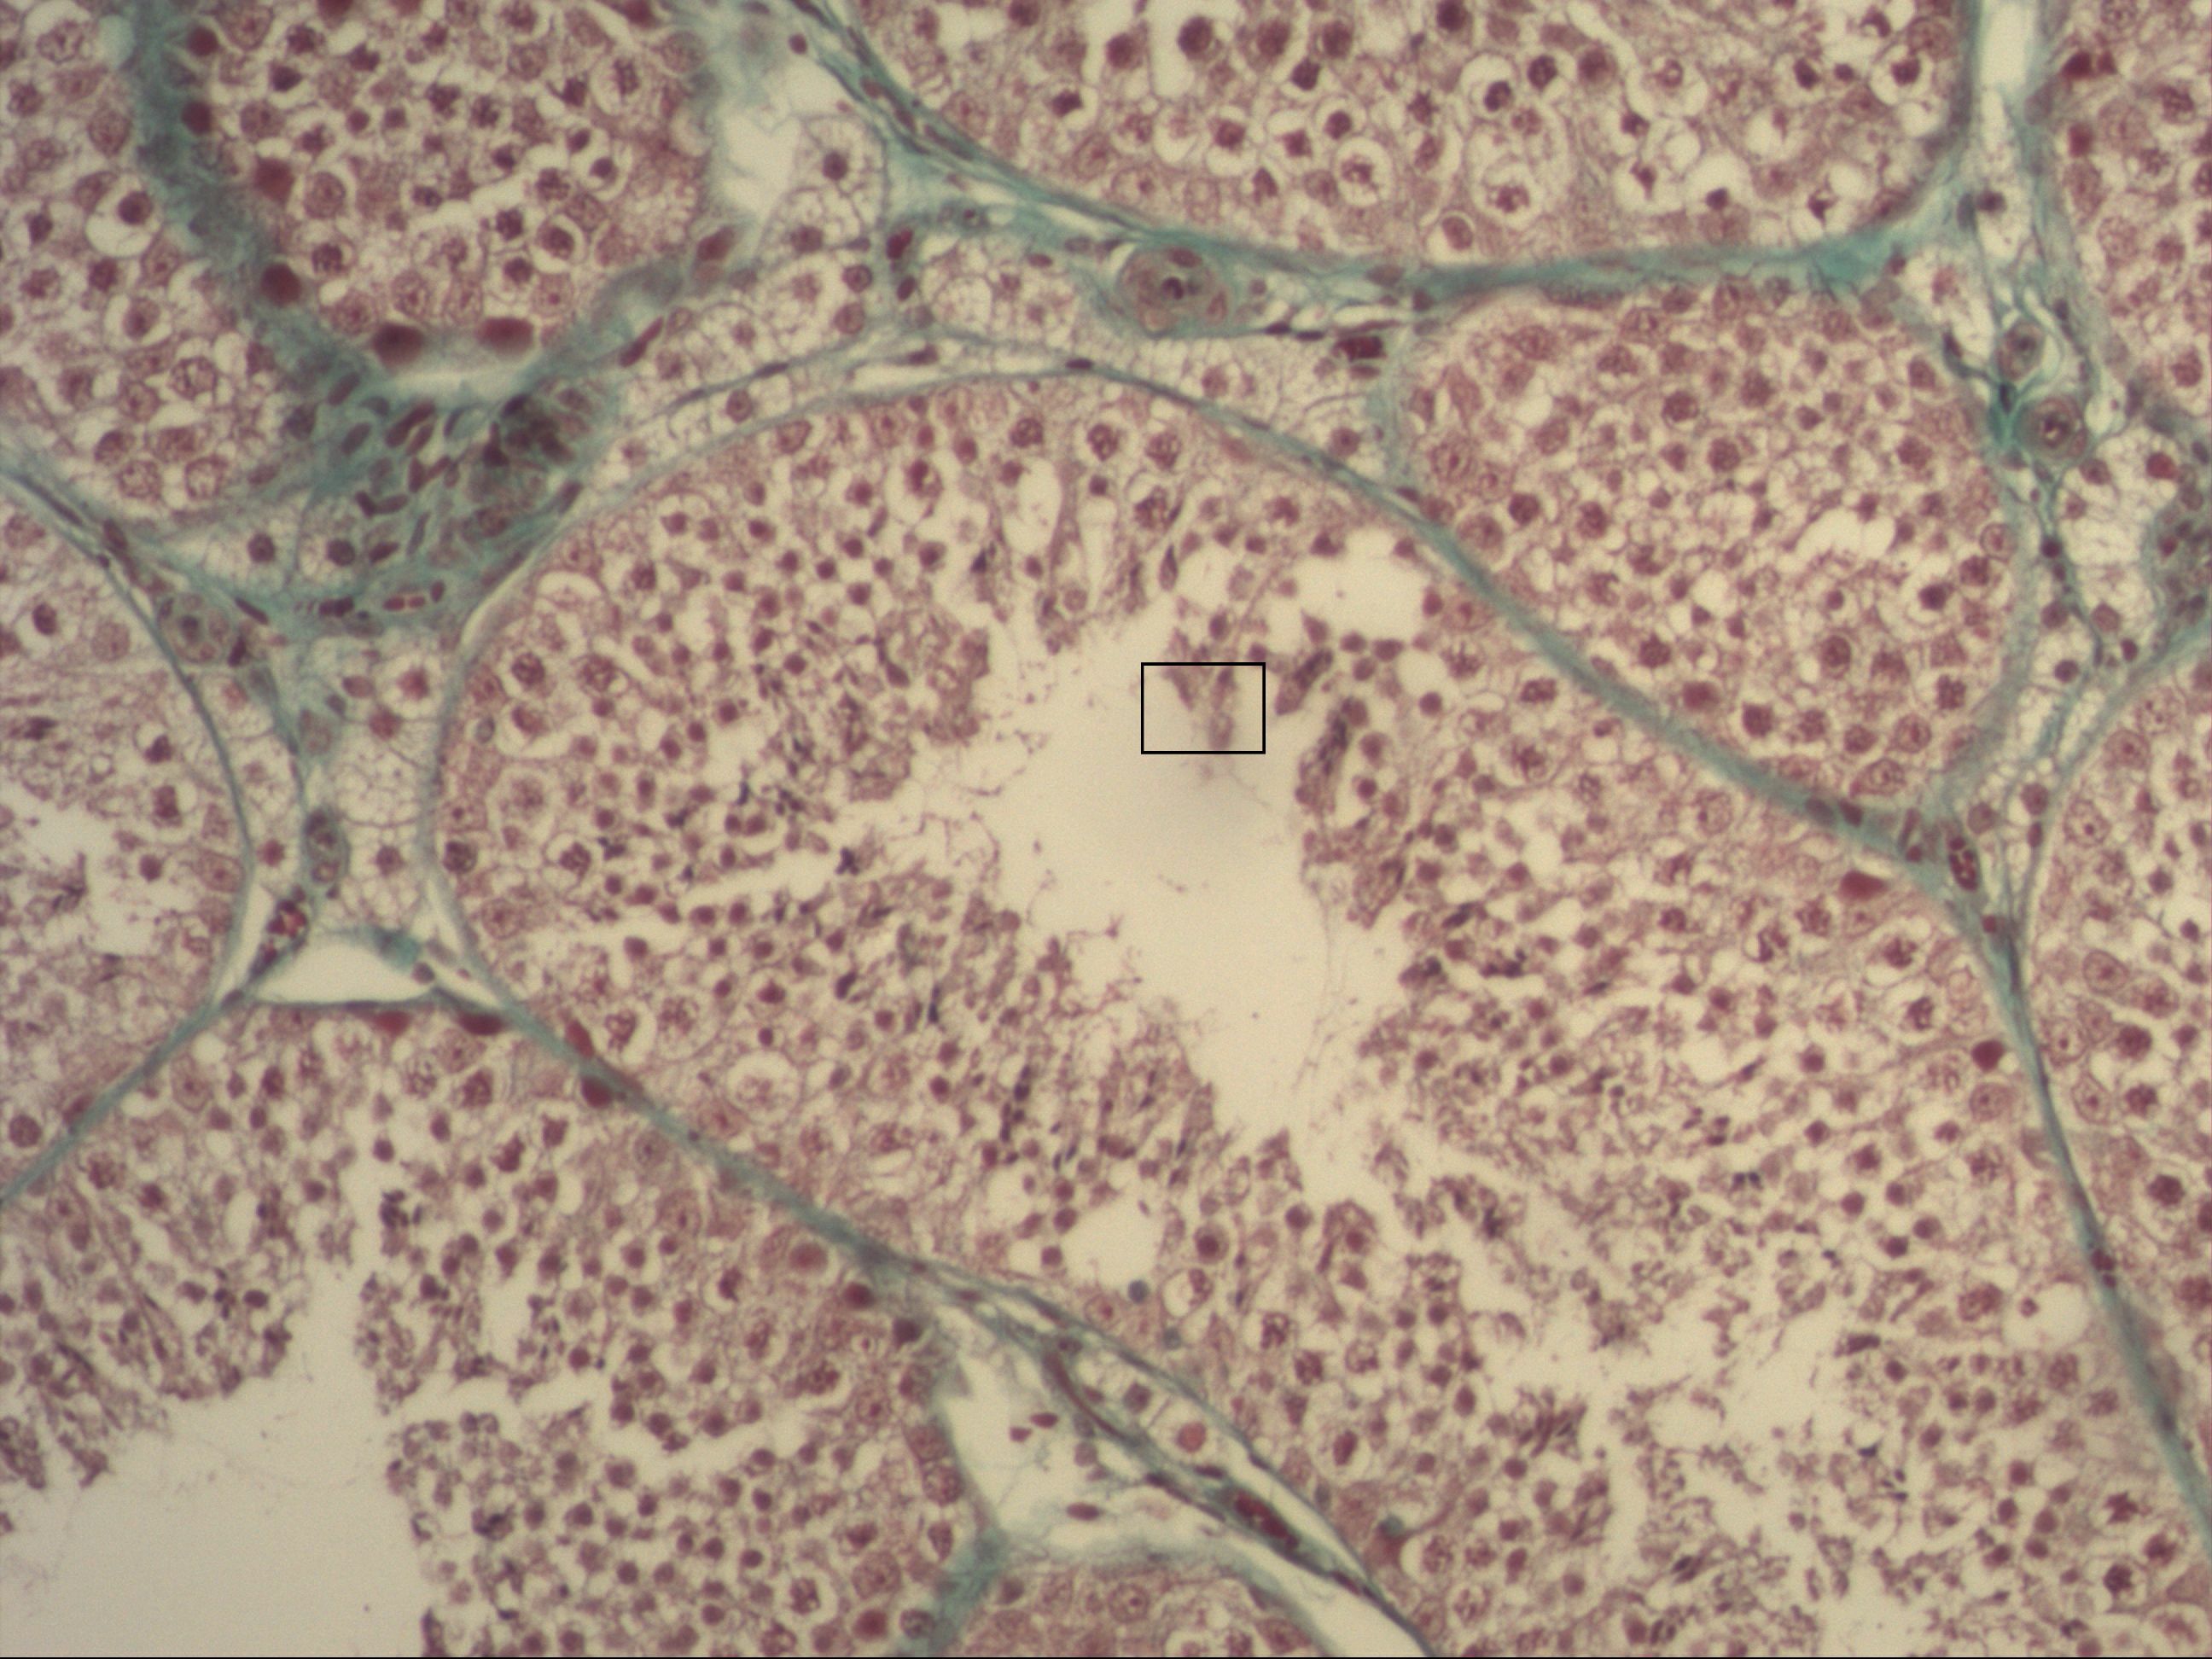

Spermatogenese

Hoden [Trichrom]

Man erkennt die Hodenkanälchen, in denen die Spermien gebildet werden. Von basal aus beginnt die Entwicklung ins Lumen hinein: Spermatogonien, Spermatozyten und Spermatiden.Die Sertoli-Zellen bilden das Epithel und gleichzeitig die Blut-Hoden-Schranke (Tight junctions).Die Leydig-Zellen befinden sich im Bindegewebe und sind für die Testosteronbildung verantwortlich.